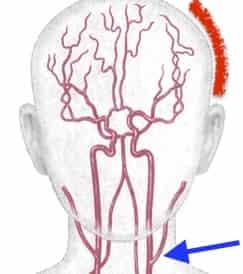

片頭痛と群発頭痛の対策

いずれも血管を冷やす事で血管が縮んで痛みが軽くなります。逆に入浴や運動など体温が上がる動作で血管が拡張して痛みが強くなります。そこで、頭痛の起きている側の首の部分を氷や保冷材などで冷やすと効果的です。痛みの部分を冷やしても、下に頭蓋骨があるため血管には届きにくいです。

脳の血管の入口は主に頚動脈という首の部分の血管です。痛みが左側であれば左側の頚動脈、右側であれば右側の頚動脈を冷やすとよいでしょう。なお、片頭痛は必ずしも片側とは限らないので、両側が痛ければ両側を冷やしてみてください。

冷やしてもだめな場合は、血管収縮薬であるトリプタン製剤などを用います。